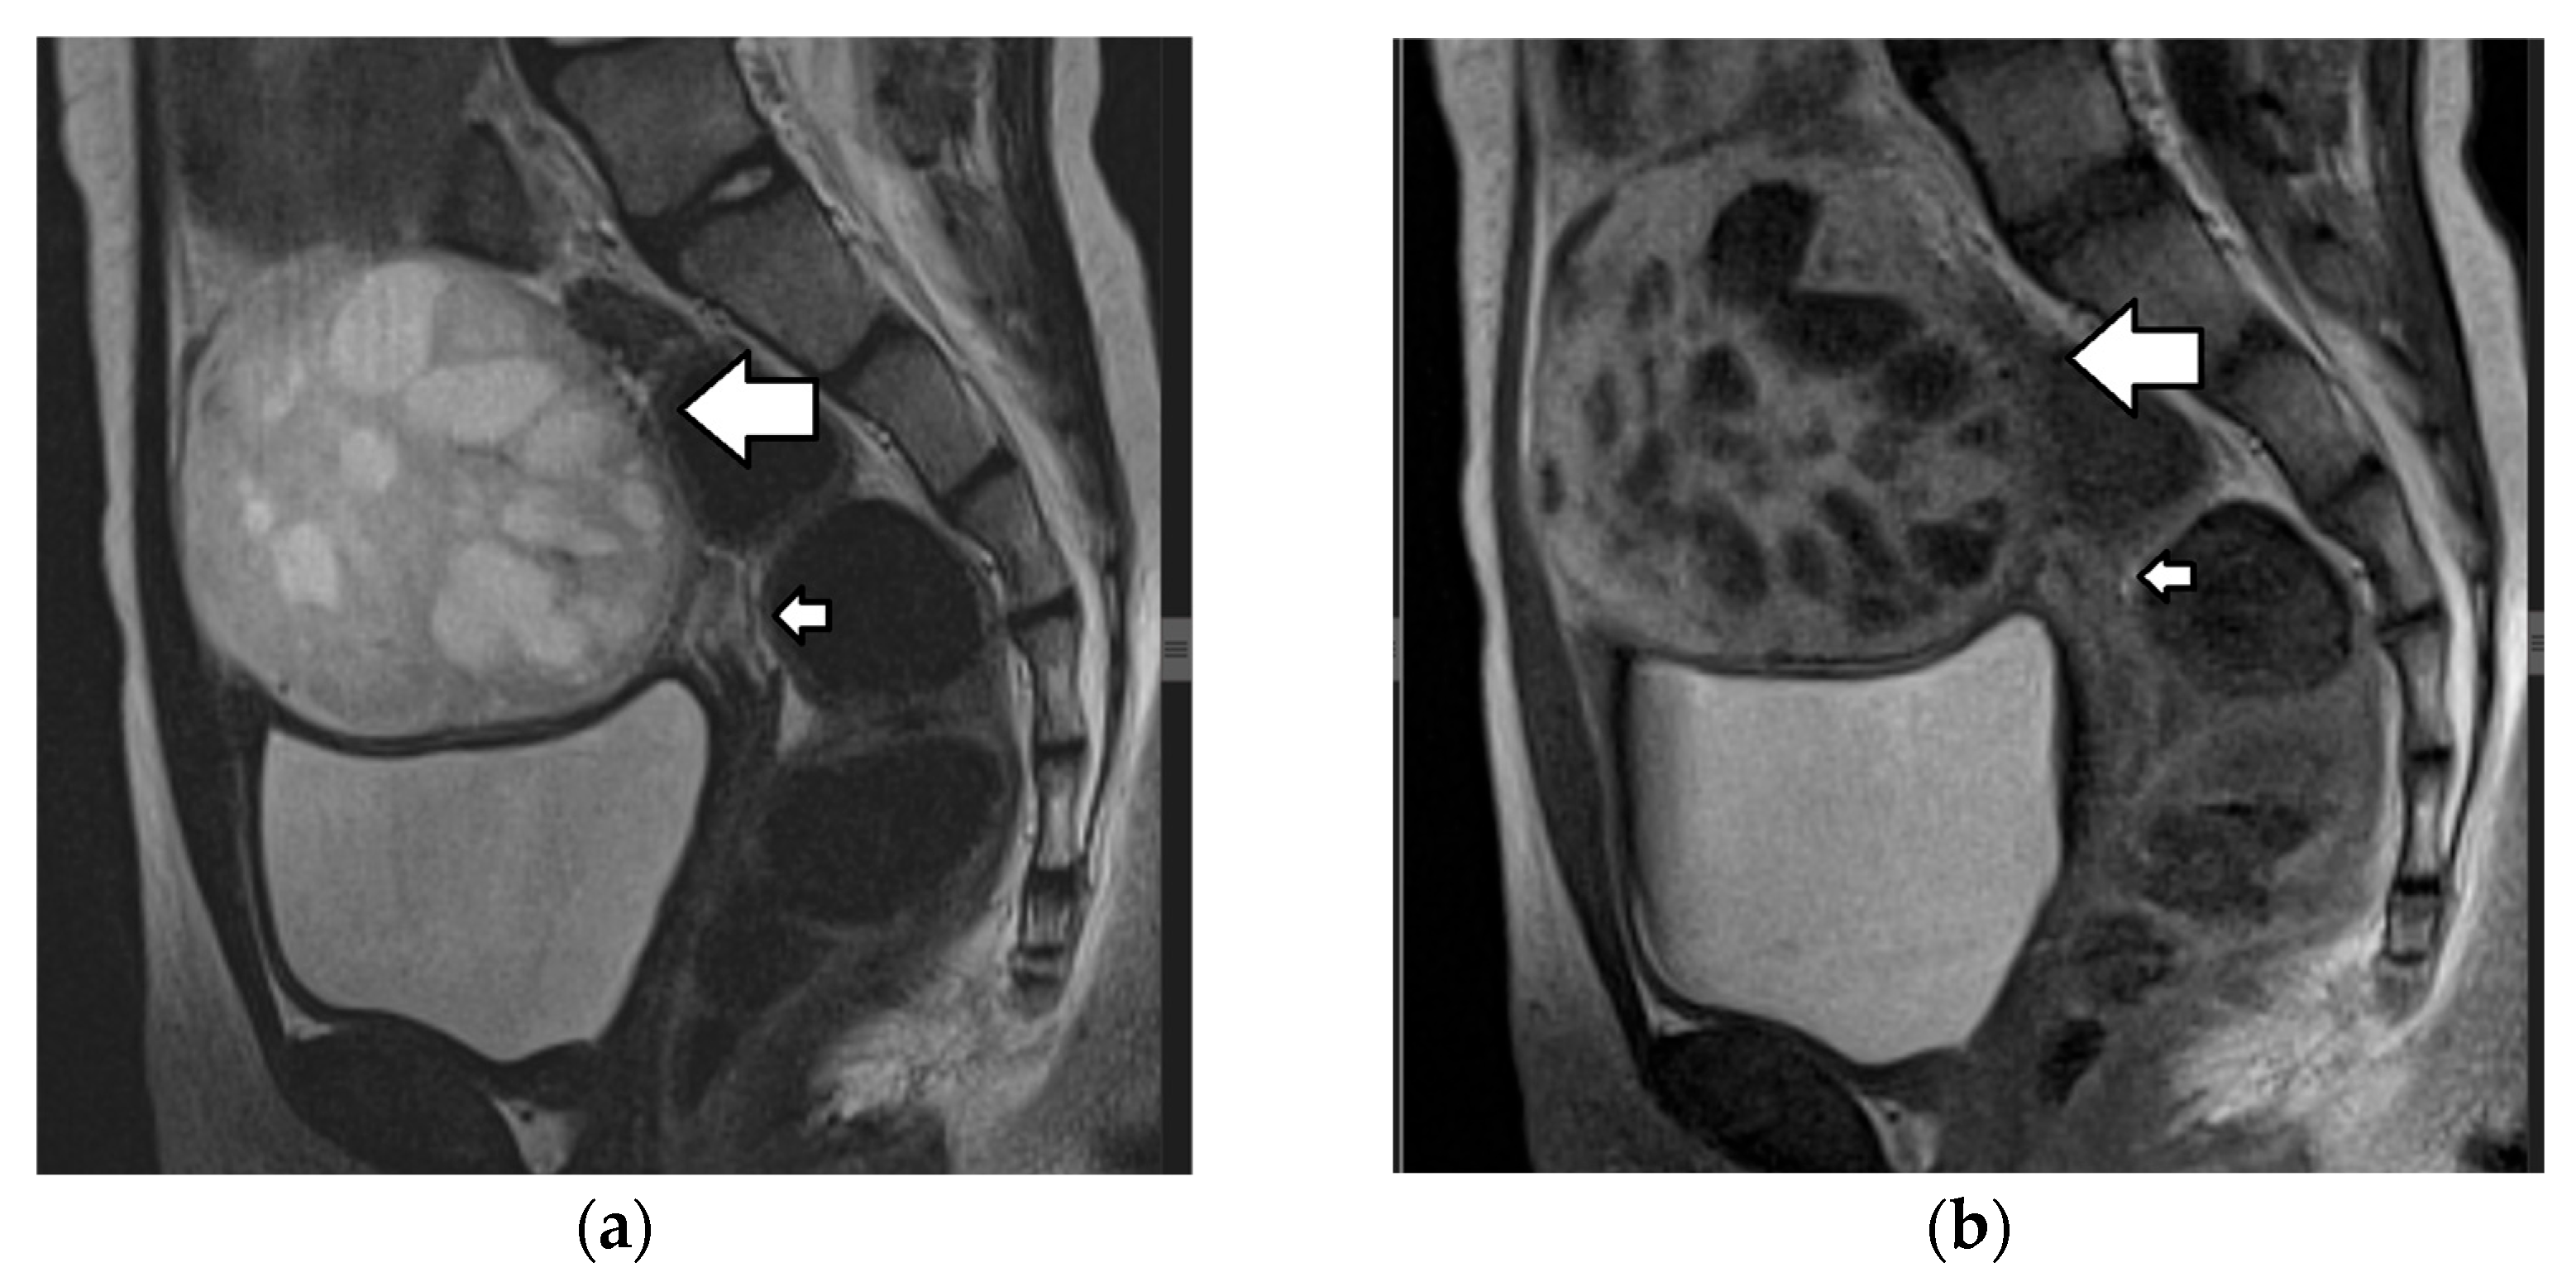

| Sertoli–Leydig cell tumor | 15% of SCSTs mean age: 14 years mostly unilateral secretes androgens: virilization secretes estrogens (rarely) association with DICER1 syndrome(moderately and poorly differentiated tumors) possible association with Peutz–Jeghers syndrome | moderately and poorly differentiated tumors: clinically malignant in 10% and 60% of cases, respectively often diagnosed at an early stage favorable prognosis recurrence rate: may be high | increased AFP (occasionally): poorly differentiated tumors with heterologous hepatocyte elements | nonspecific predominantly solid vascular tumor, with numerous peripheral or intratumoral cysts or cystic, with solid components MRI

|